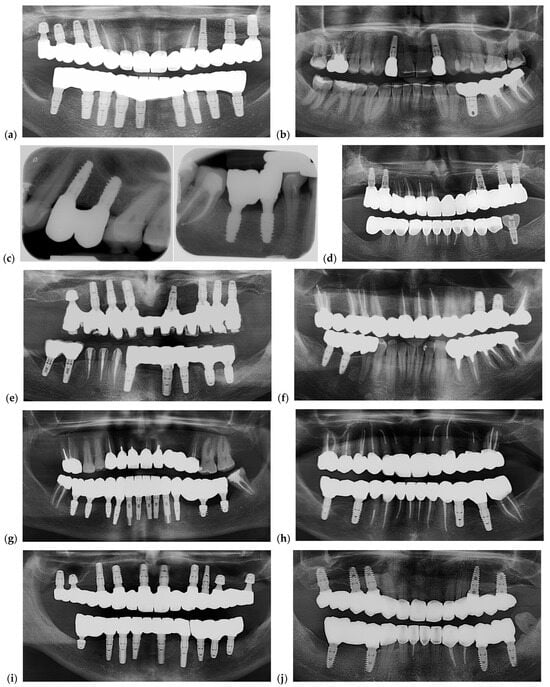

A representative example of restorations fabricated with and without prosthetic caps is illustrated in Figure 2 to demonstrate the restorative configurations compared in this study.

Figure 2.

Clinical and radiographic comparison of screw-retained full-arch restorations fabricated with and without prosthetic caps. (a) Clinical photo of a maxillary full-arch screw-retained restoration, (b) clinical photo of a mandible full-arch screw-retained restoration, (c) section of an OPG corresponding to (a), (d) section of an OPG corresponding to (b). Blue lines are between implant sites with caps, while yellow lines are between implant sites with caps. (e) is the OPG of the final delivered restorations.

Photos of 5 restorations from selected cases for each group are presented in Figure 16. Radiographic images are shown in Figure 17. Each image from Figure 16 is corresponding with the same position of the Figure 17.

Figure 16.

Pictures of dental restorations with (a,c,e,g,i) or without (b,d,f,h,j) the PKT from cases selected for this study.

Figure 17.

Representative radiographs illustrating the seating and adaptation of the analyzed restorations after fixation. (a,c,e,g,i) Restorations with the PKT cap; (b,d,f,h,j) restorations without the PKT cap. Panoramic radiographs were primarily used to document overall fit and implant distribution, while periapical radiographs (panel (c)) were included only in one representative case to confirm marginal seating and screw engagement at higher resolution. All radiographs served as qualitative confirmation of restoration fit following final torque, not for quantitative gap measurement. Each radiograph corresponds to photos in Figure 16.

Both panoramic and periapical radiographs were used to verify restoration seating after fixation. Panoramic views documented overall prosthetic alignment, while periapical images (in one case) confirmed marginal fit and screw engagement at higher resolution